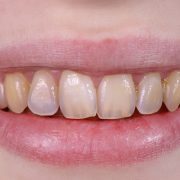

- تغییر رنگ دندان ها که ممکن است خود را به صورت لکه دار شدن نشان دهد

- ایجاد نوعی ساختار رنگی روی سطح دندان ها

- تغییر رنگ سطح دندان ها و اصطلاحاً دندان های زرد رنگ

- ایجاد لکه های رنگی و قابل رویت روی دندان

- از بین رفتن تدریجی مینای دندان که منجر به شفاف بودن و براق بودن دندان ها می شود